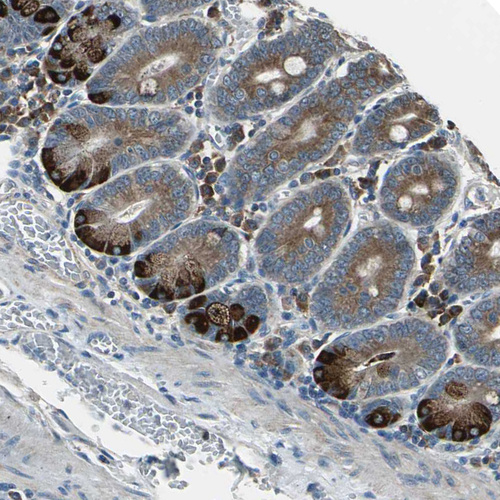

Immunohistochemical staining of human spleen shows moderate cytoplasmic positivity in sinusoids.